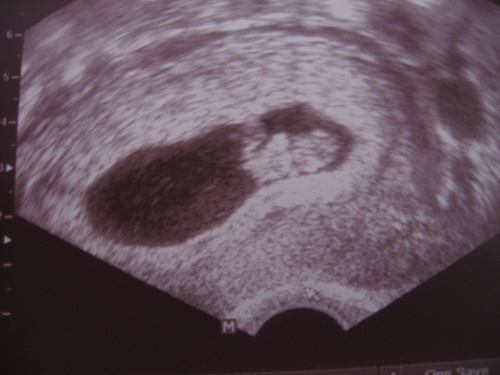

Igaz a nőgyogyinál se voltam még a terhesség igazolása sincs meg.